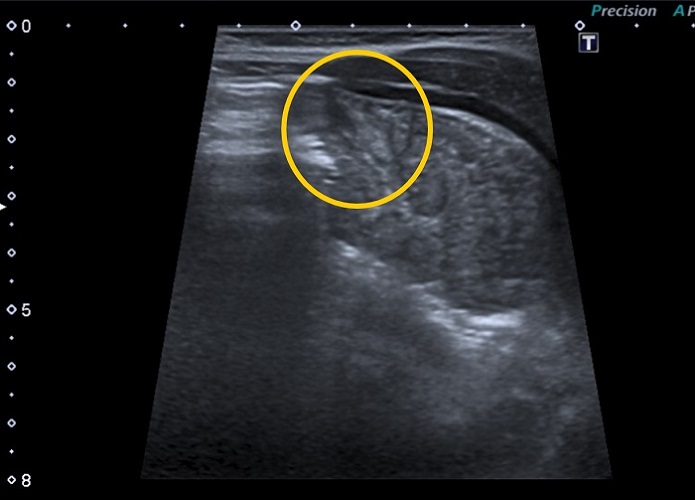

Se administra paracetamol por vía oral y se queda en observación. Mantiene irritabilidad por lo que se decide realización de radiografía y ecografía abdominal, sin hallazgos relevantes salvo discreta elevación de hemidiafragma izquierdo con abundante gas en estómago (Fig. 1).

| Figura 1. Hernia diafragmática congénita de presentación tardía (paciente de 6 meses): radiografía de abdomen con imagen aérea subdiafragmática |

Se completa el estudio con una analítica, sin alteraciones, y una radiografía de tórax (Fig. 2) informada como consolidación basal izquierda sin poder descartar derrame pleural, motivo por el cual se decide realizar ecografía torácica donde se observa una imagen compatible con una hernia diafragmática congénita izquierda (Fig. 3).